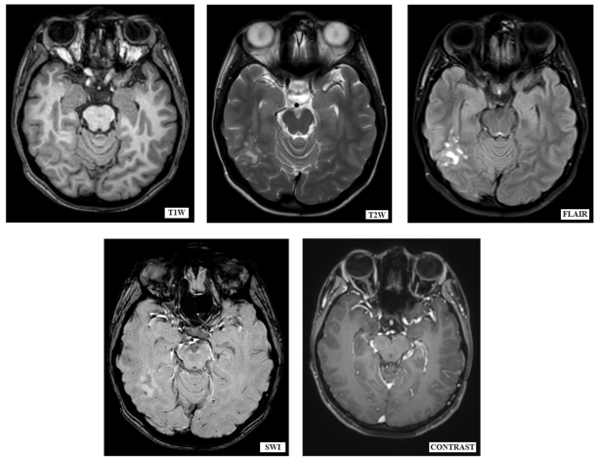

MRI brain with contrast (Figure.1)

Figure 1: MRI Brain plain and contrast of the patient that shows a cluster of coalescent nodules in the posterior aspect of right temporal and right tempero-parietal lobes.

Was done, that revealed a small cluster of well defined, high T2W/ FLAIR weighted coalescent nodules in the subcortical and periventricular white matter of the posterior aspect of right temporal and right tempero-parietal lobes. Overlying cortex is not thickened which was suggestive of multinodular vacuolating neuronal tumor.

On CT imaging, they are difficult to identify, yet as described by Nagaishi et al4., in some patients they are seen as hypo dense and non-enhancing lesion in the subcortical white matter. MRI is considered as gold standard imaging for these lesions. They are seen as a group of nodules on the inner surface of the cortex. Nodules are hyperintense to the adjacent white matter on T2W and FLAİR images. They are isointense or mildly hypointense on T1W. They typically exhibit no diffusion restriction or contrast enhancement. They demonstrate no blooming on susceptibility-weighted imaging.